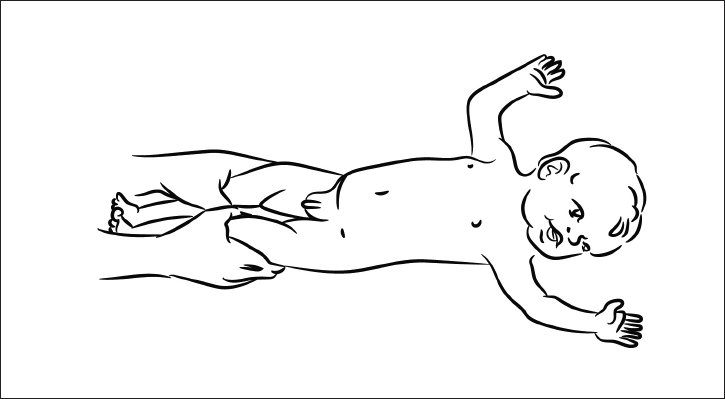

2. Рефлекс разгибания головы

При переворачивании на живот ребенок вытягивает ноги, разгибает туловище и далее разгибает голову (рис. 18).

Рис. 18. Рефлекс разгибания головы.

Это движение обеспечивается активацией длинных разгибателей шеи. Благодаря ему ребенок, который лежит на животе, не задыхается.

У взрослого человека он постепенно переходит в рефлекс поддержания головы в вертикальном положении, а мышцы-разгибатели формируют заднюю МФЦ (рис. 19).